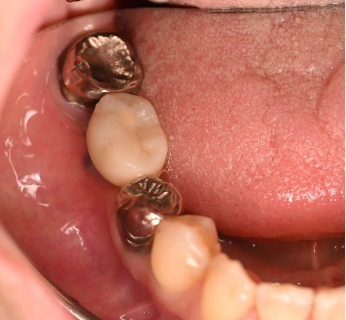

右下奥の歯が、グラグラして噛むと痛い。

治療内容

歯根の周りの骨が全く無い状態でしたので、保存することができず抜歯しました。3本歯がないところに2本インプラントを埋入しました。

インプラント2本:¥363,000×2本=¥726,000(税込)

ポンティック1本:¥115,500(税込)

合計:¥841,500(税込)

Before

※赤丸を抜歯しました。

After